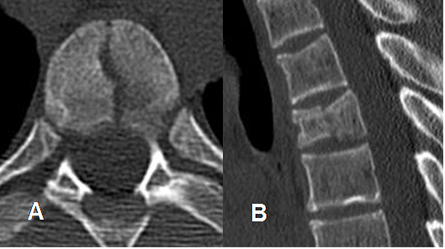

Fig 185. Fractura inestable.

A: TAC axial y B: TAC reconstrucción sagital. Fractura con compromiso de la columna anterior y media, quedando el cuerpo vertebral dorsal dividido en 2 mitades.